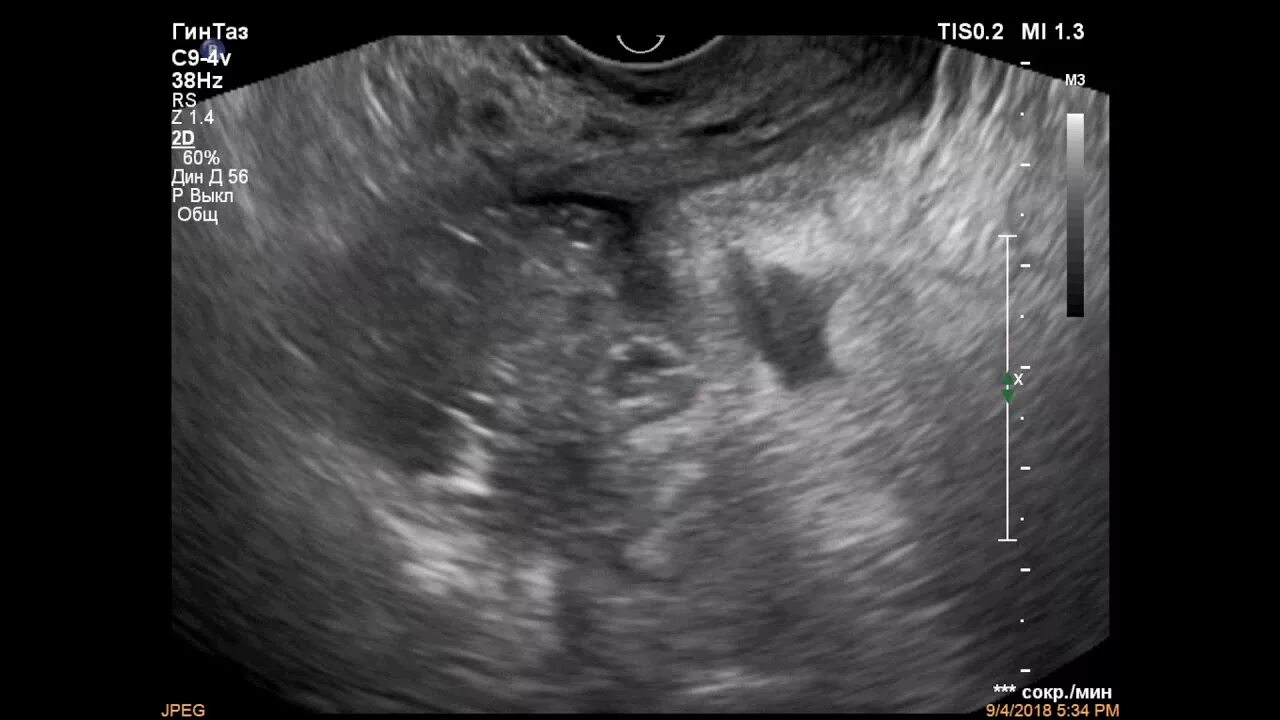

Какое узи при аппендиците